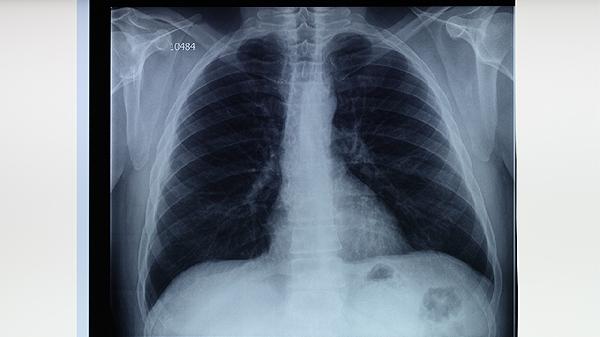

补肺丸可通过抗炎和抗氧化作用减轻肺泡损伤,延缓肺纤维化进程,对慢性阻塞性肺疾病患者的肺活量、通气功能有一定改善作用。需配合呼吸康复训练,定期监测肺功能指标调整用药方案。